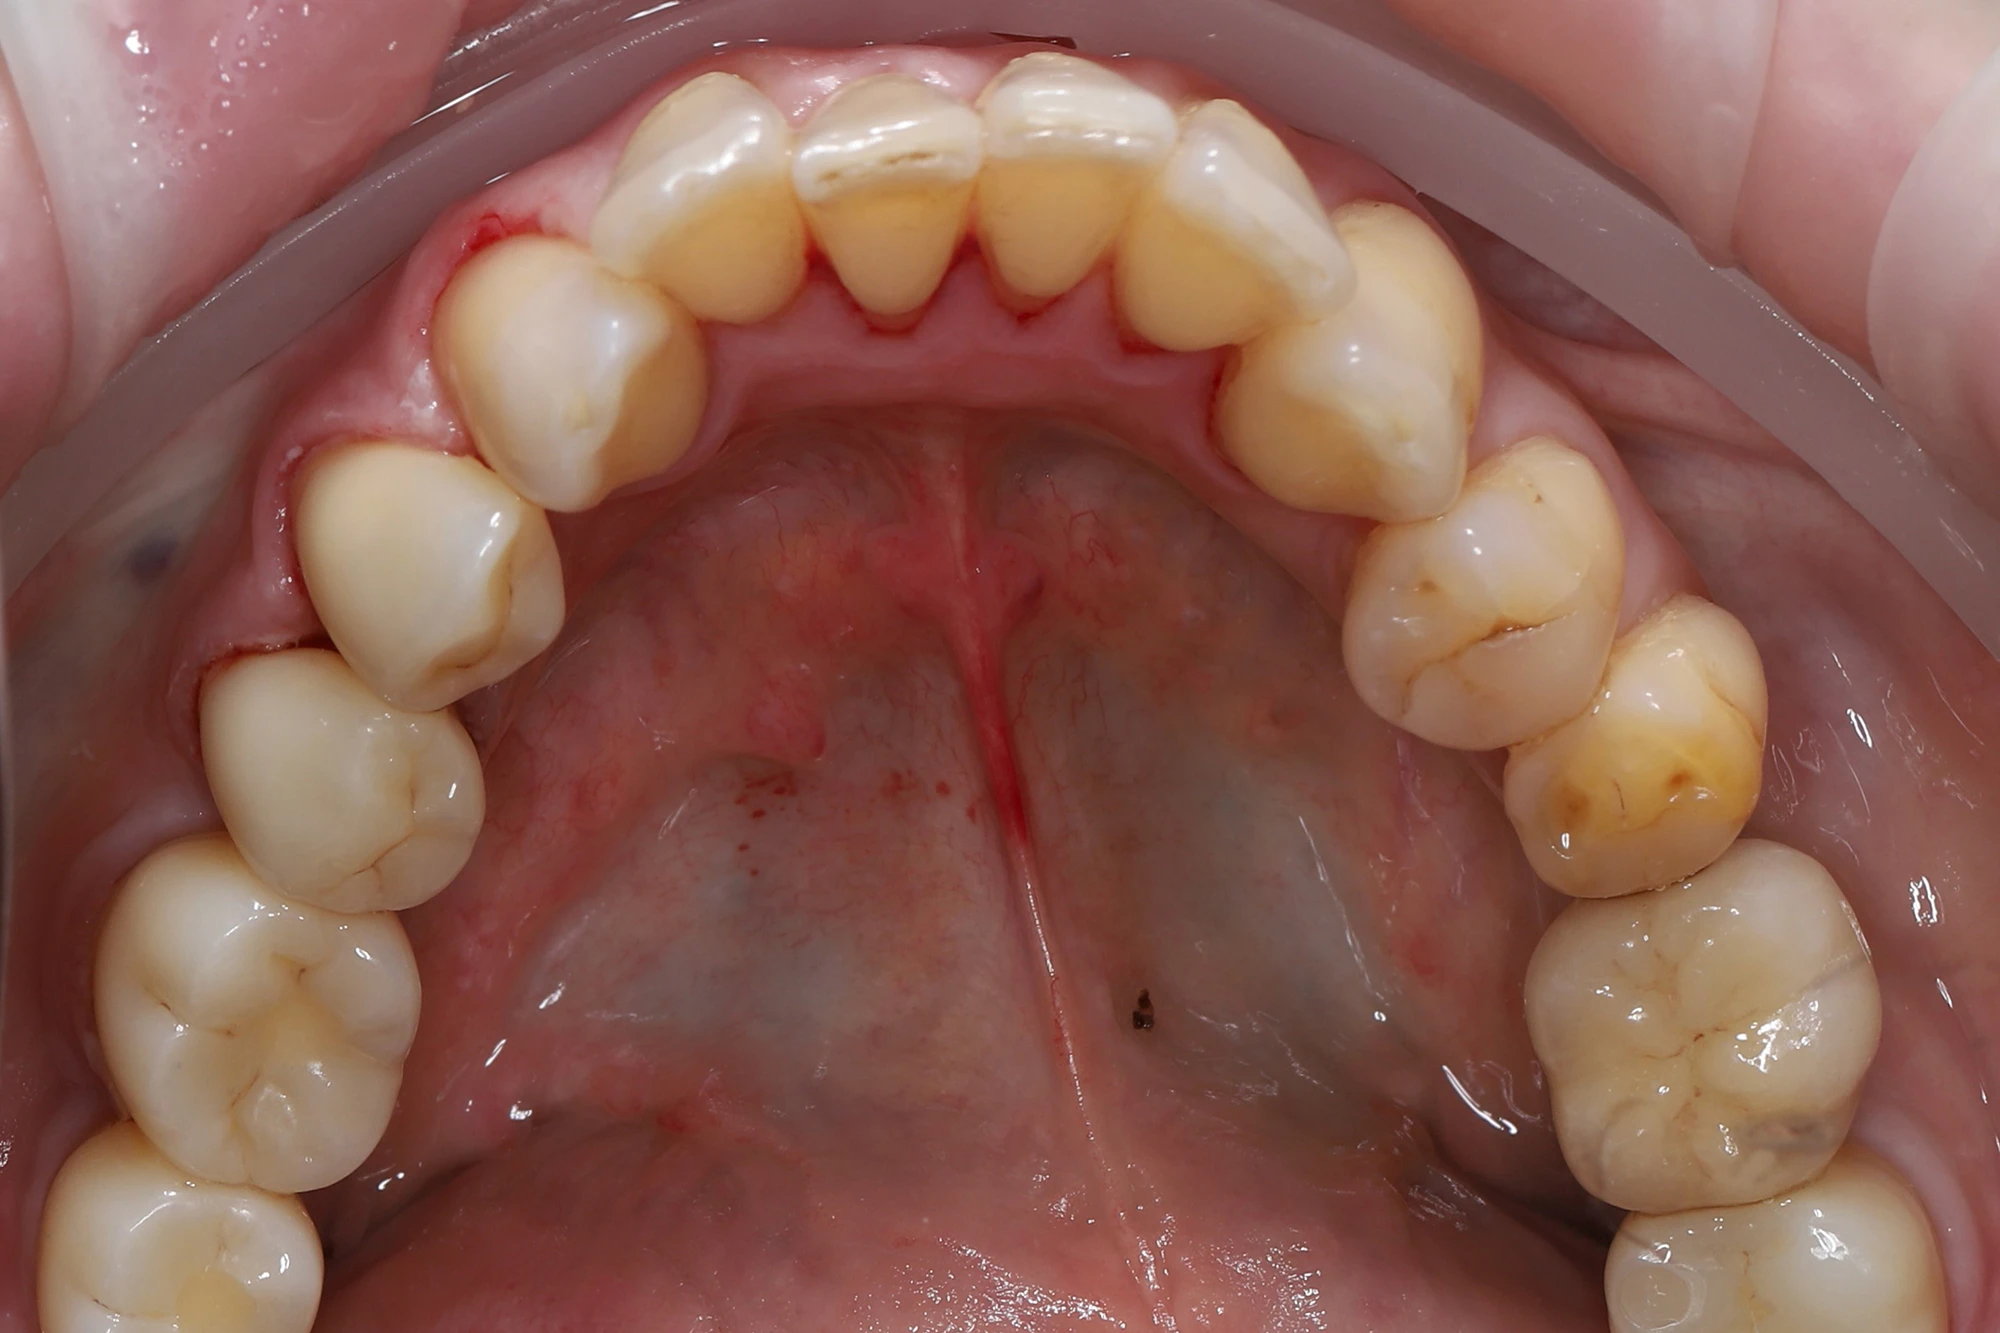

Заживление прошло без осложнений, слизистая бледно-розового цвета. Через

3 месяца была выполнена контрольная рентгенография: костный уровень сохранен, признаков воспаления нет, имплантаты остеоинтегрированы. Проведено раскрытие имплантатов и установлены индивидуализированные формирователи десны.